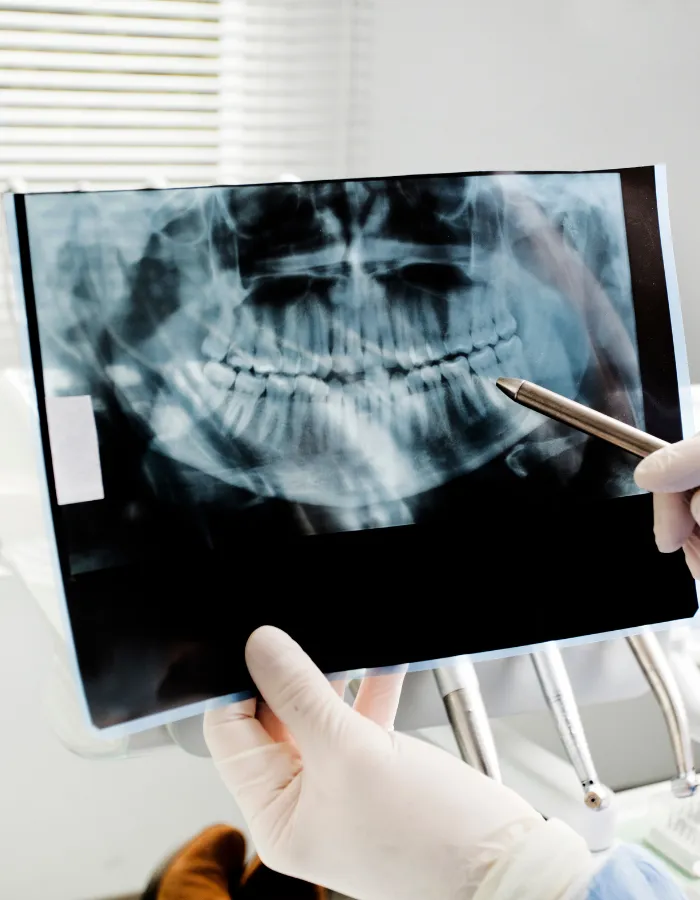

Dental X-Rays

About Dental X-Rays

At The Global Dentist, we provide advanced dental X-rays in Islamabad using modern, low-radiation digital technology. Our clinic in G-8 Markaz, Islamabad, offers safe and precise dental imaging to detect problems early and plan effective treatments. Patients searching for a dentist near me, a dental clinic near G-8 Markaz, or a trusted dentist in Islamabad choose us for our accurate diagnosis, patient comfort, and expert dental care.

Located at Chohan Plaza, G-8 Markaz, Islamabad, our clinic offers high-quality Dental X-Rays in a comfortable and welcoming environment.